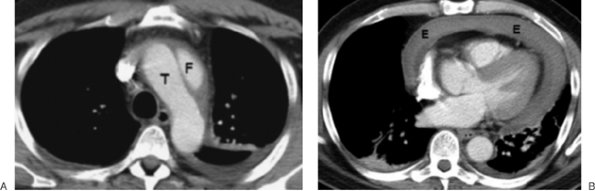

Aortic dissections are collections of blood within the media of the aortic wall that communicate with the true aortic lumen through one or more tears in the intima. Most dissections begin within an intimal tear, and bleeding splits the aortic media. Two classification systems are used to describe aortic dissection. The DeBakey classification divides aortic dissection into three types (15). Type I refers to dissections that start in the ascending aorta and extend into the descending aorta; type II, to dissections confined to the ascending aorta; and type III, to dissections that start just beyond the left subclavian artery and are confined to the descending aorta. The Stanford classification refers to type A (involving the ascending aorta) and type B (confined to the descending aorta) (16). The diagnostic feature of aortic dissection on contrast-enhanced CT scanning is two lumina separated by an intimal flap (Fig. 6-28). The intimal flap is seen as a curvilinear low-attenuation area within the opacified aorta. A false lumen usually fills and empties in a delayed fashion compared with a true lumen. The false lumen may be partially or totally filled by thrombus and therefore may not opacify. The true lumen is usually compressed by the false lumen. Displacement of calcified atheromatous plaques by the dissection can be demonstrated on precontrast CT scans when contrast enhancement of the two lumina cannot be achieved (as with a thrombosed false lumen). Aortic dissection is further discussed along with other aortic pathology in Chapter 19.

FIGURE 6-28. Aortic dissection. A: CT scan shows two aortic lumina - a false lumen (F) and a true lumen (T) - separated by an intimal flap. B: CT scan at a more inferior level shows a pericardial effusion (E) that is of high attenuation, indicating hemorrhage.